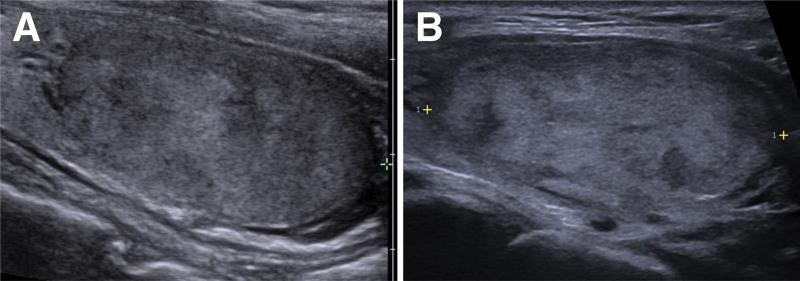

A 45-year-old female without documented comorbidities presented a thyroid nodule during a routine health examination. Initial evaluation revealed a 3.8-cm nodule in the left lobe of thyroid, classified as Bethesda System category III on fine needle aspiration cytology. Genetic molecular testing detected the BRAF V600E mutation via quantitative polymerase chain reaction assay, raising concern for papillary thyroid cancer (PTC).

一位 45 岁的女性,无已知合并症,在常规健康检查中发现甲状腺结节。初步评估显示左叶甲状腺有一个 3.8 厘米的结节,在细针穿刺细胞学检查中归类为 Bethesda 系统类别 III。基因分子检测通过定量聚合酶链反应检测到 BRAF V600E 突变,这引发了对甲状腺乳头状癌(PTC)的担忧。